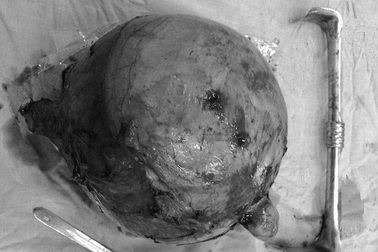

Người phụ nữ mang khối u xơ tử cung nặng 3kg, tương đương một thai nhiNgày 6/8, thông tin từ Bệnh viện Đa khoa khu vực Quảng Nam (phường Điện Bàn, thành phố Đà Nẵng), bác sĩ của đơn vị đã phẫu thuật, cắt tử cung toàn phần cho một bệnh nhân mắc u xơ tử cung hiếm gặp.

"Bóc" khối u xơ tử cung gần 3,6kg ra khỏi cơ thể bệnh nhânBSCK II Nguyễn Quốc Hùng- Giám đốc Bệnh viện Sản- Nhi Quảng Ninh cho biết, các bác sĩ của vừa phẫu thuật thành công, "bóc" một khối u xơ tử cung “khổng lồ” với trọng lượng 3,59kg.

Phẫu thuật khối u xơ tử cung nặng gần 8kgChiều 25/4 nguồn tin từ bệnh viện Phụ sản TP Cần Thơ cho biết các bác sĩ của bệnh viện này đã phẫu thuật thành công cho bệnh nhân bị u xơ tử cung to với cân nặng khối u lên đến 7,8kg.

Khối u xơ tử cung nặng gần 6kg sau 3 nămBệnh viện Phụ sản thành phố Cần Thơ tiếp nhận bệnh nhân Đ.T.T (42 tuổi), cư trú tại Vĩnh Long. Bệnh nhân T. nhập viện trong tình trạng bụng lớn và bị ra máu âm đạo.